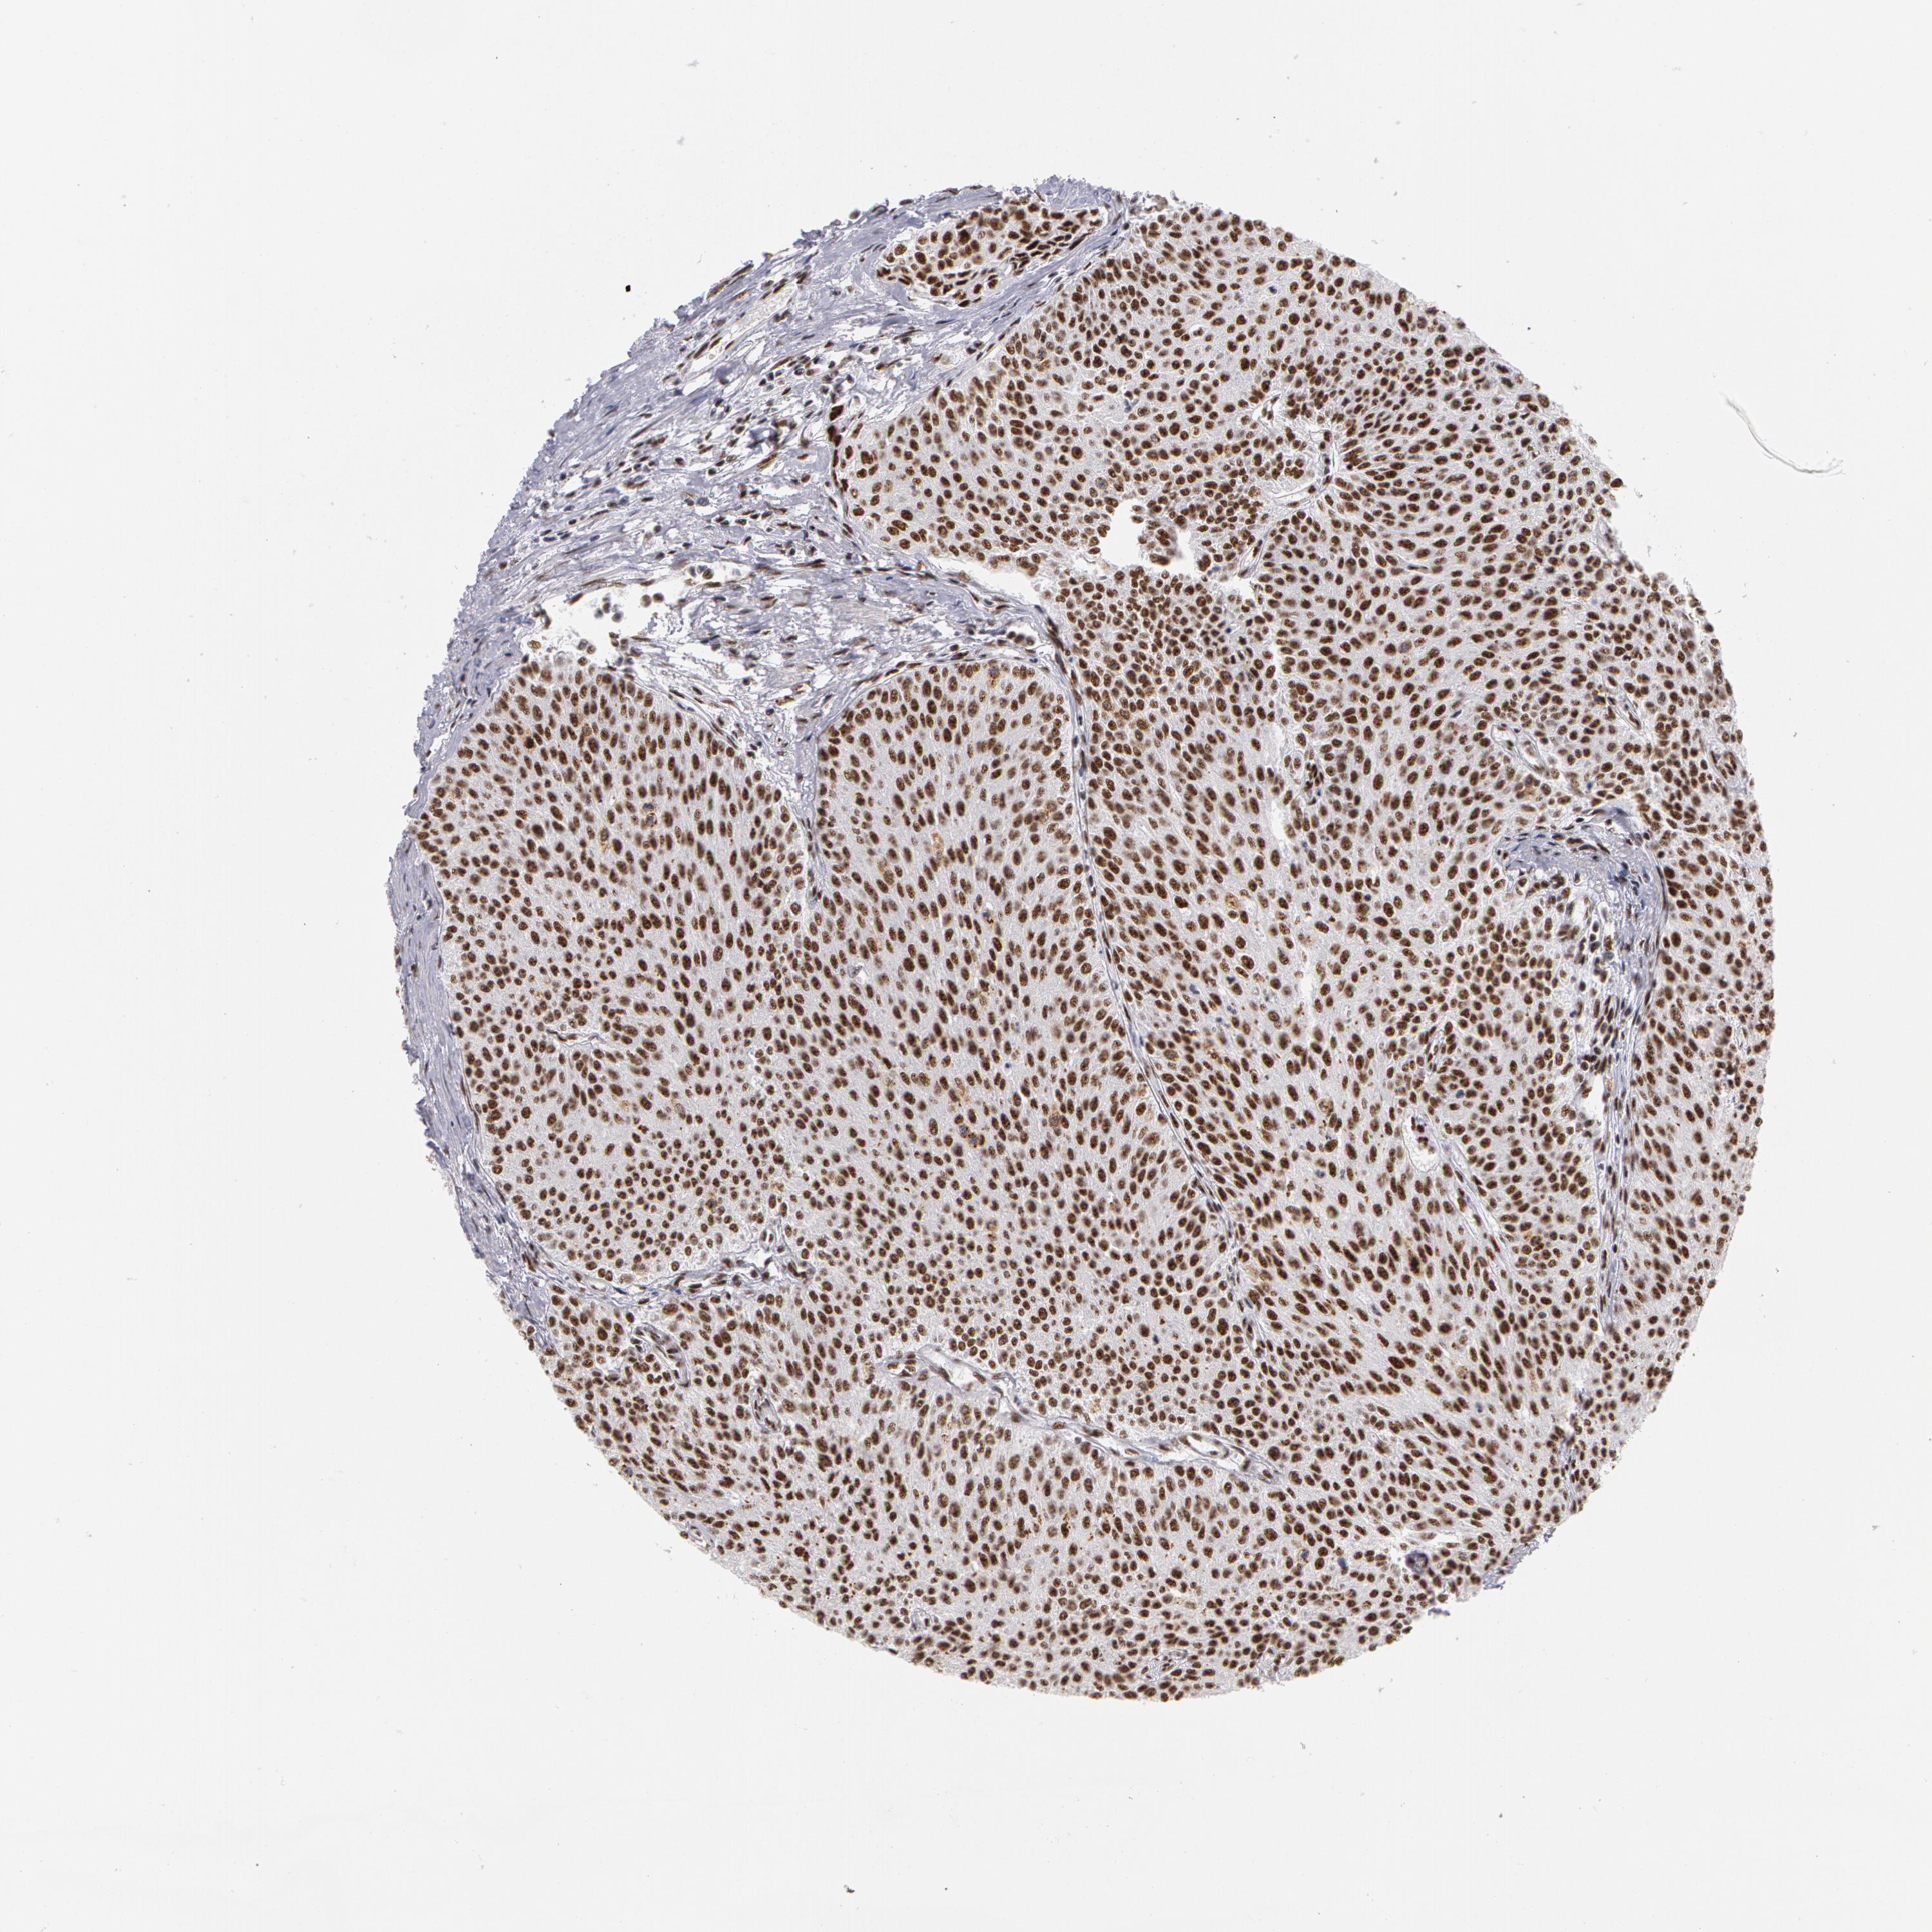

UROTHELIAL CANCER - Protein expressioni

A mouse-over function shows sample information and annotation data. Click on an image to view it in a full screen mode. Samples can be filtered based on level of antibody staining by selecting one or several of the following categories: high, medium, low and not detected. The assay and annotation is described here.

Note that samples used for immunohistochemistry by the Human Protein Atlas do not correspond to samples in the TCGA dataset.

Antibody stainingi

Antibody staining in the annotated cell types in the current human tissue is reported as not detected, low, medium, or high, based on conventional immunohistochemistry profiling in selected tissues. This score is based on the combination of the staining intensity and fraction of stained cells.

Each image is clickable and will lead to virtual microscopy that enables deeper exploration of all samples and also displays staining intensity scores, fraction scores and subcellular localization as well as patient and tissue information for each sample.

Antibody HPA001378

Staining

High

Medium

Low

Not detected

Intensity

Strong

Moderate

Weak

Negative

Quantity

>75%

75%-25%

<25%

None

Location

Nuclear

Cytoplasmic/membranous

Cytoplasmic/membranous,nuclear

Urothelial carcinoma, High grade